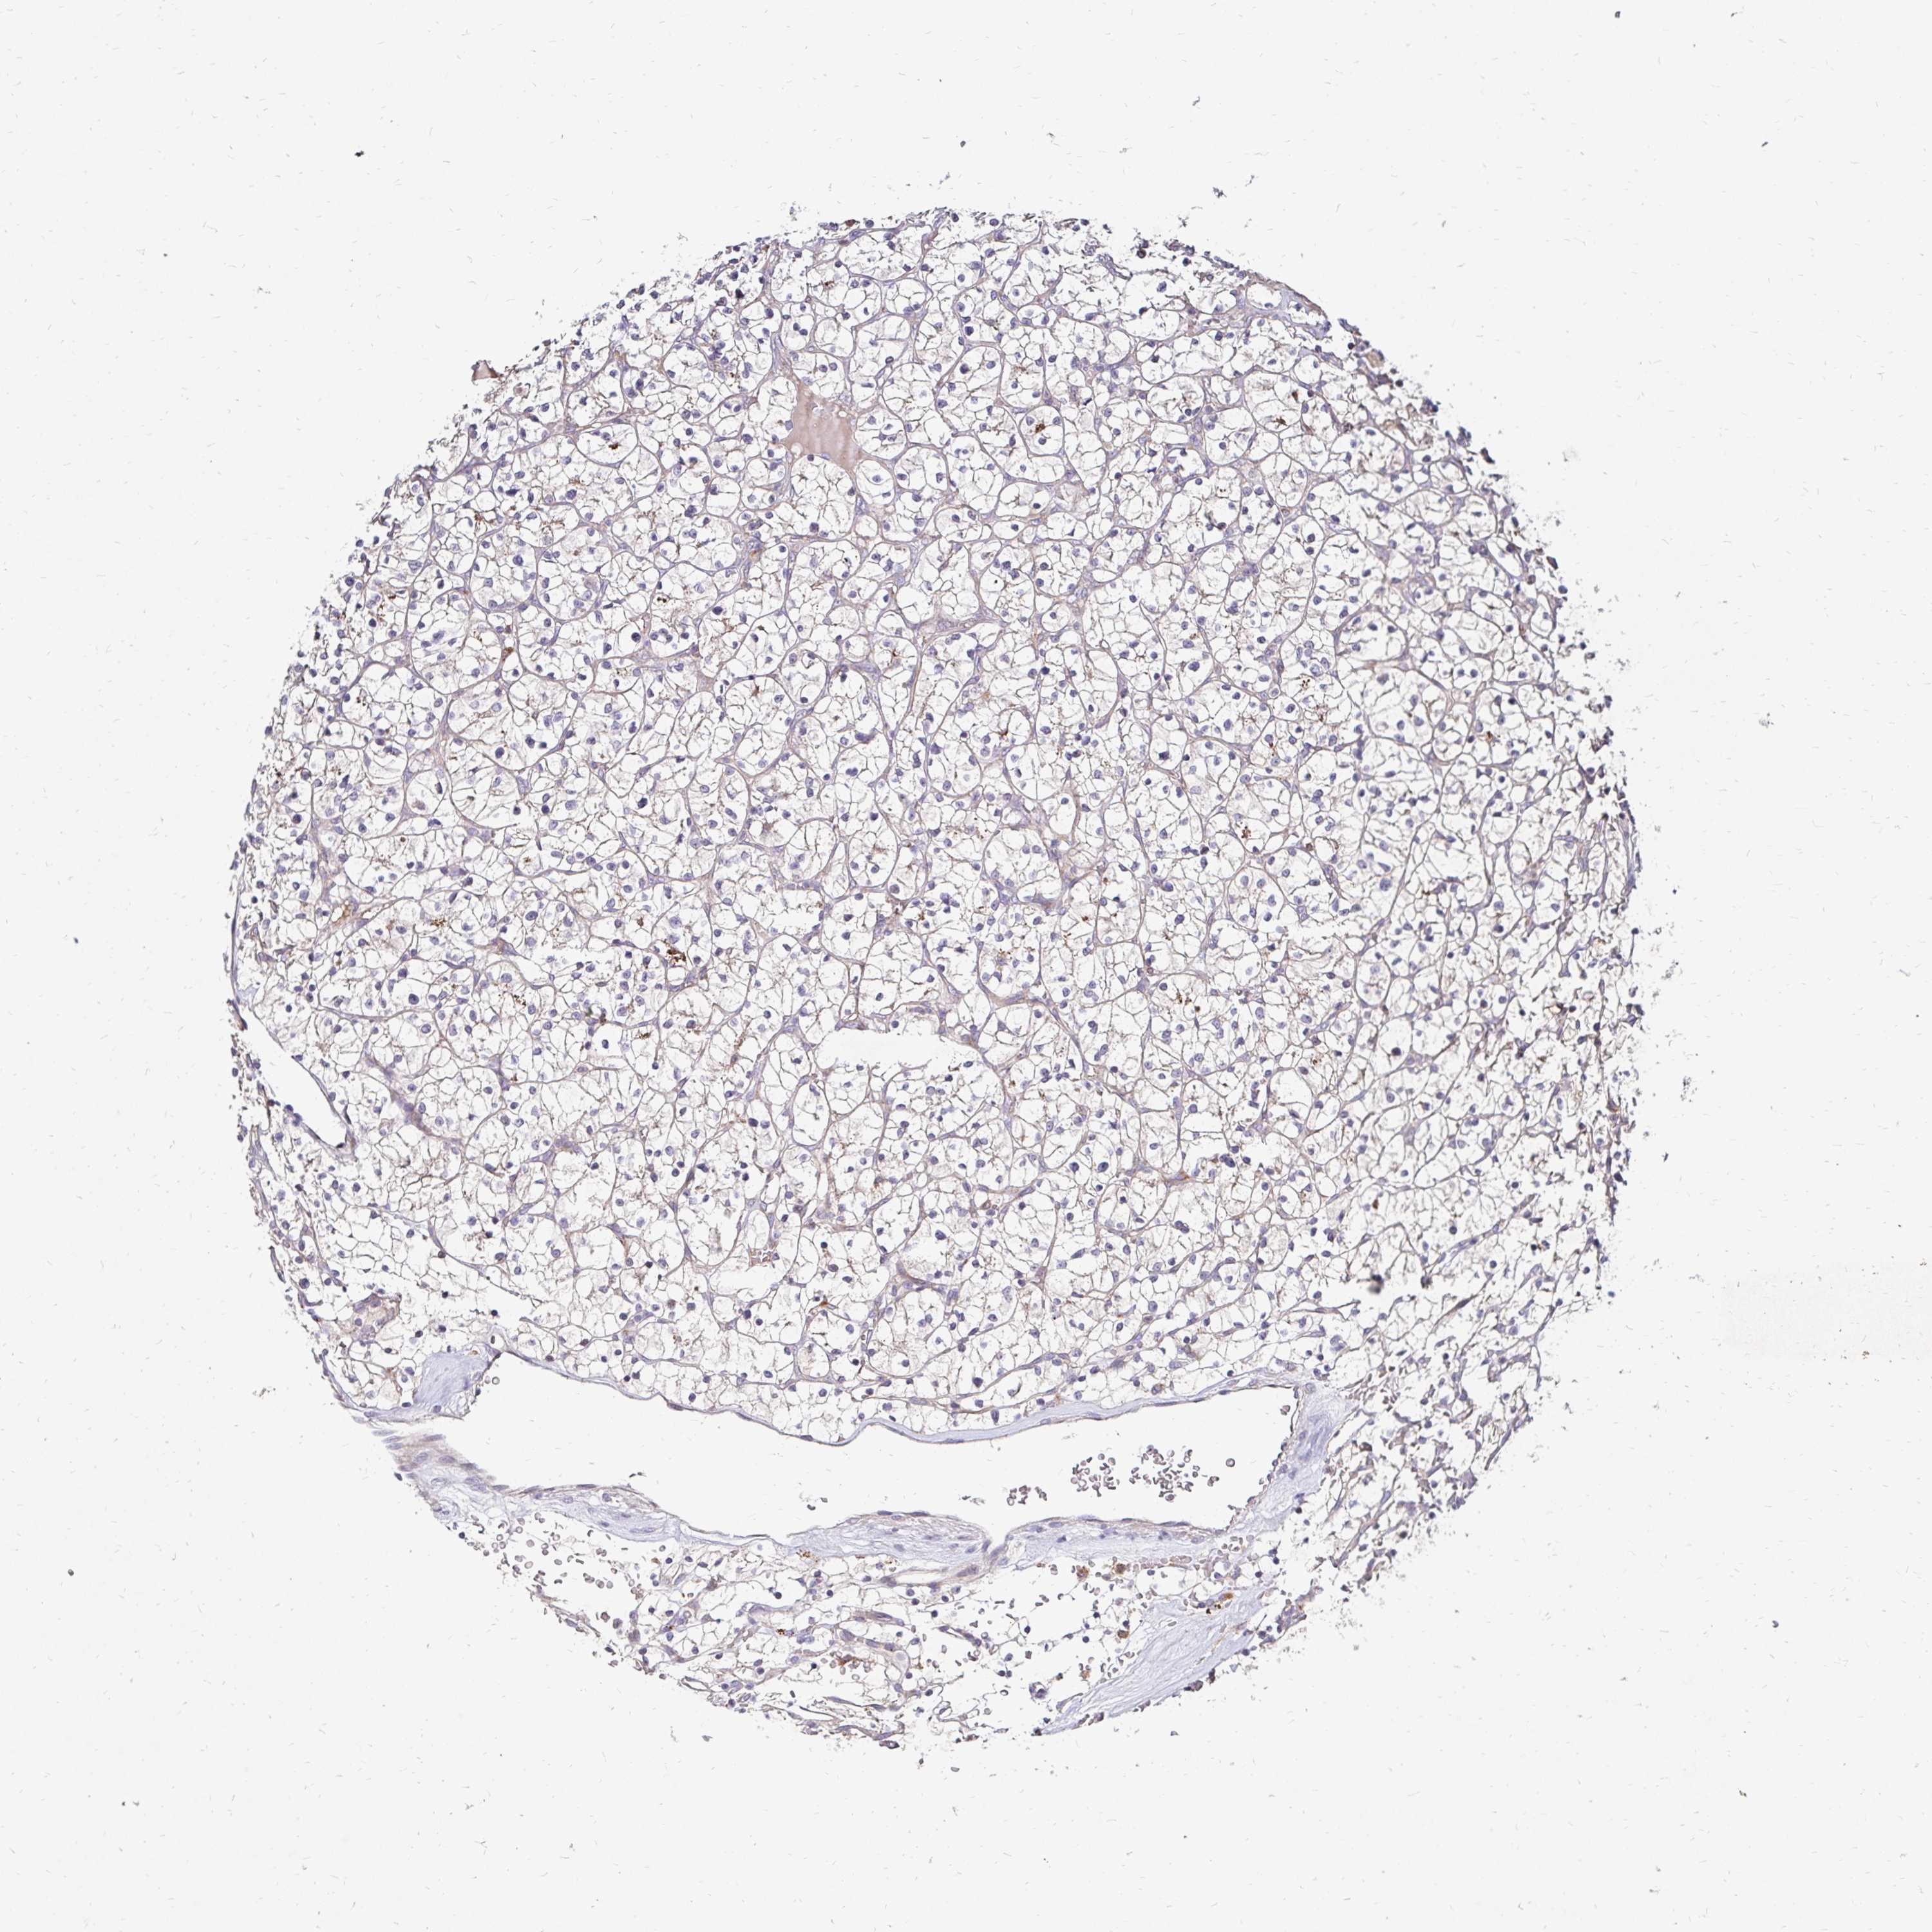

KIDNEY RENAL PAPILLARY CELL CARCINOMA (TCGA) - Interactive survival scatter ploti

The Survival Scatter plot shows the clinical status (i.e. dead or alive) for all individuals in the patient cohort, based on the same data that underlies the corresponding Kaplan-Meier plots. Patients that are alive at last time for follow-up are shown in blue and patients who have died during the study are shown in red.

The x-axis shows the expression levels (FPKM) of the investigated gene in the tumor tissue at the time of diagnosis. The y-axis shows the follow-up time after diagnosis (years). Both axes are complimented with kernel density curves demonstrating the data density over the axes. The top density plot shows the expression levels (FPKM) distribution among dead (red) and alive patients (blue). The right density plot shows the data density of the survived years of dead patients with high and low expression levels respectively, stratified using the cutoff indicated by the vertical dashed line through the Survival Scatter plot. This cutoff is automatically defined based on the FPKM cutoff that minimizes the p-score. The cutoff can be changed by dragging the vertical line or by entering a cutoff value in the square labeled "Current cut-off".

Under the Survival Scatter plot the p-score landscape (black curve; left axis) is shown together with dead median separation (red curve; right axis). Dead median separation is the difference in median mRNA expression between patients who have died with high and low expression, respectively. It is calculated as follows: median FPKM expression of dead patients with high expression - median FPKM expression of dead patients with low expression. This is intended to aid the user in visually exploring custom cutoffs and the associated p-scores and dead median separation.

Individual patient data is displayed and can be filtered by clicking on one or more of the category buttons on the top of the page. Categories describing expression level and patient information include: high, low, alive, dead, female, male and tumor stages. The scale of the x-axis can be toggled between linear and log-scale by clicking on the "x log" button. Mouse-over function shows TCGA ID, patient information and mRNA expression (FPKM) for each patient.

& Survival analysisi

Kaplan-Meier plots summarize results from analysis of correlation between mRNA expression level and patient survival. Patients were divided based on level of expression into one of the two groups "low" (under cut off) or "high" (over cut off). X-axis shows time for survival (years) and y-axis shows the probability of survival, where 1.0 corresponds to 100 percent.

IDUA is not prognostic in Kidney Renal Papillary Cell Carcinoma (TCGA)